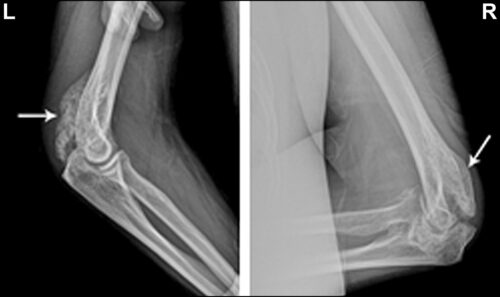

TOH のさらなる検査には、通常、股関節を詳細に観察するための画像スキャンが含まれます。 X 線、 CT 、およびMRIスキャンでは、股関節上部の大腿骨頭の骨密度のわずかな減少が示される場合があります。

MRI スキャンでは、TOH の場合によく見られる骨髄浮腫と呼ばれる異常が検出される場合もあります。骨髄浮腫は、ほとんどの骨の内部に存在する海綿状組織である骨髄が液体で満たされると発生します。